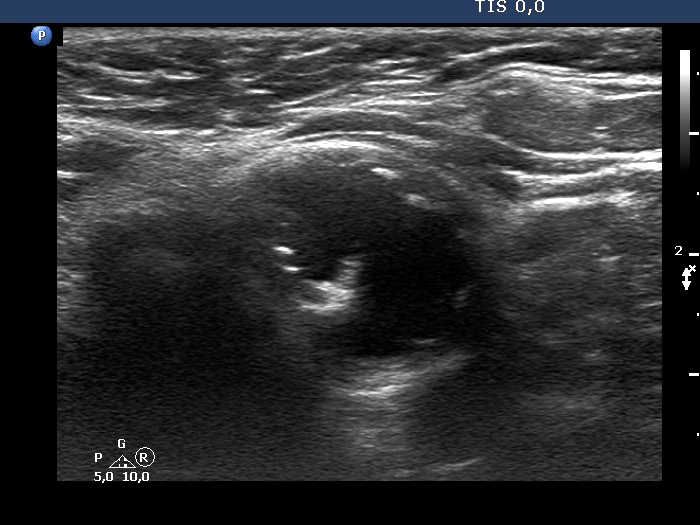

Examination 7 years later (ultrasonographic picture 4)

Lower part of the left lobe, transverse scan. There is a cystic lesion in the lower pole of the lobe.